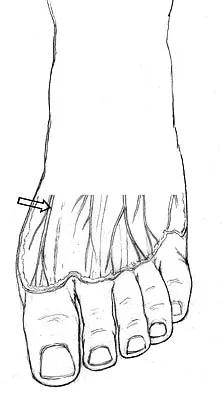

The dorsal digital cutaneous nerve of the great toe shown in Figure 8 is a branch of what nerve?

Explanation:

The dorsal digital cutaneous nerve of the great toe is a branch of the medial branch of the superficial peroneal nerve. The deep peroneal nerve supplies the first web space. McMinn RMH, Hutchings RT, Logan BM: Color Atlas of Foot and Ankle Anatomy. Weert, Netherlands, Wolfe Medical Publications, 1982, p 50.